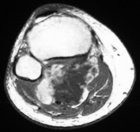

56 year old WM with right intermittent throbbing knee pain, four months ago he noticed a pop, pain, and swelling in his right knee while running, since then it has been swollen from knee to ankle, pain is getting worse

Zoom image: Radiological image Radiological image.